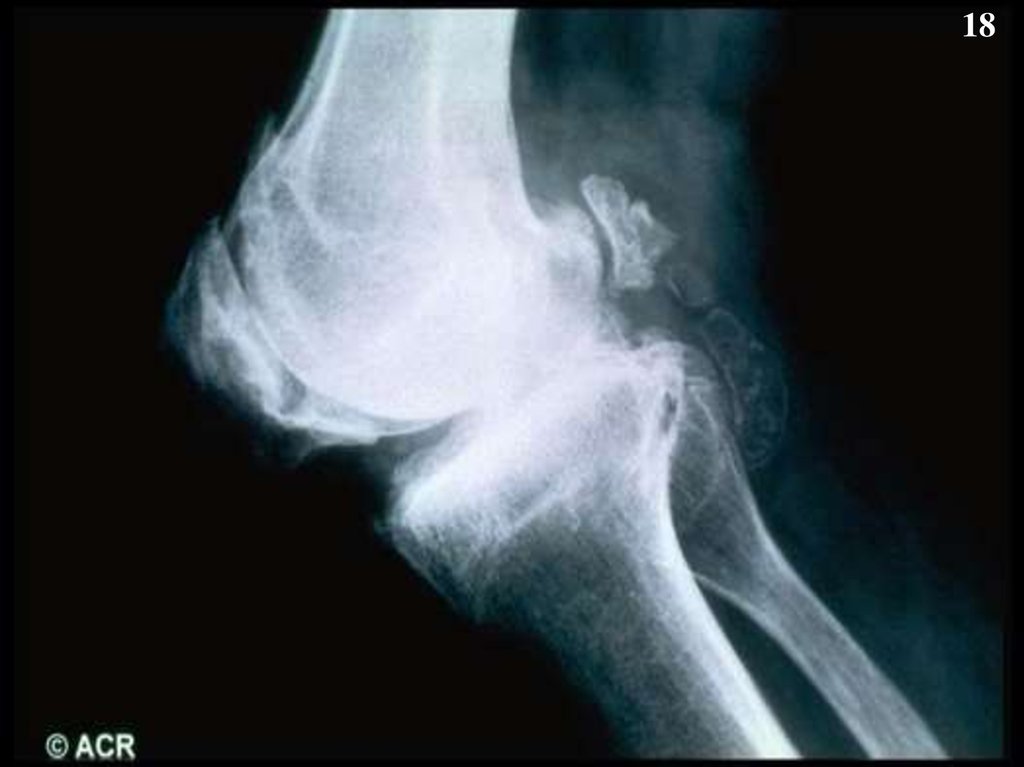

18.

18